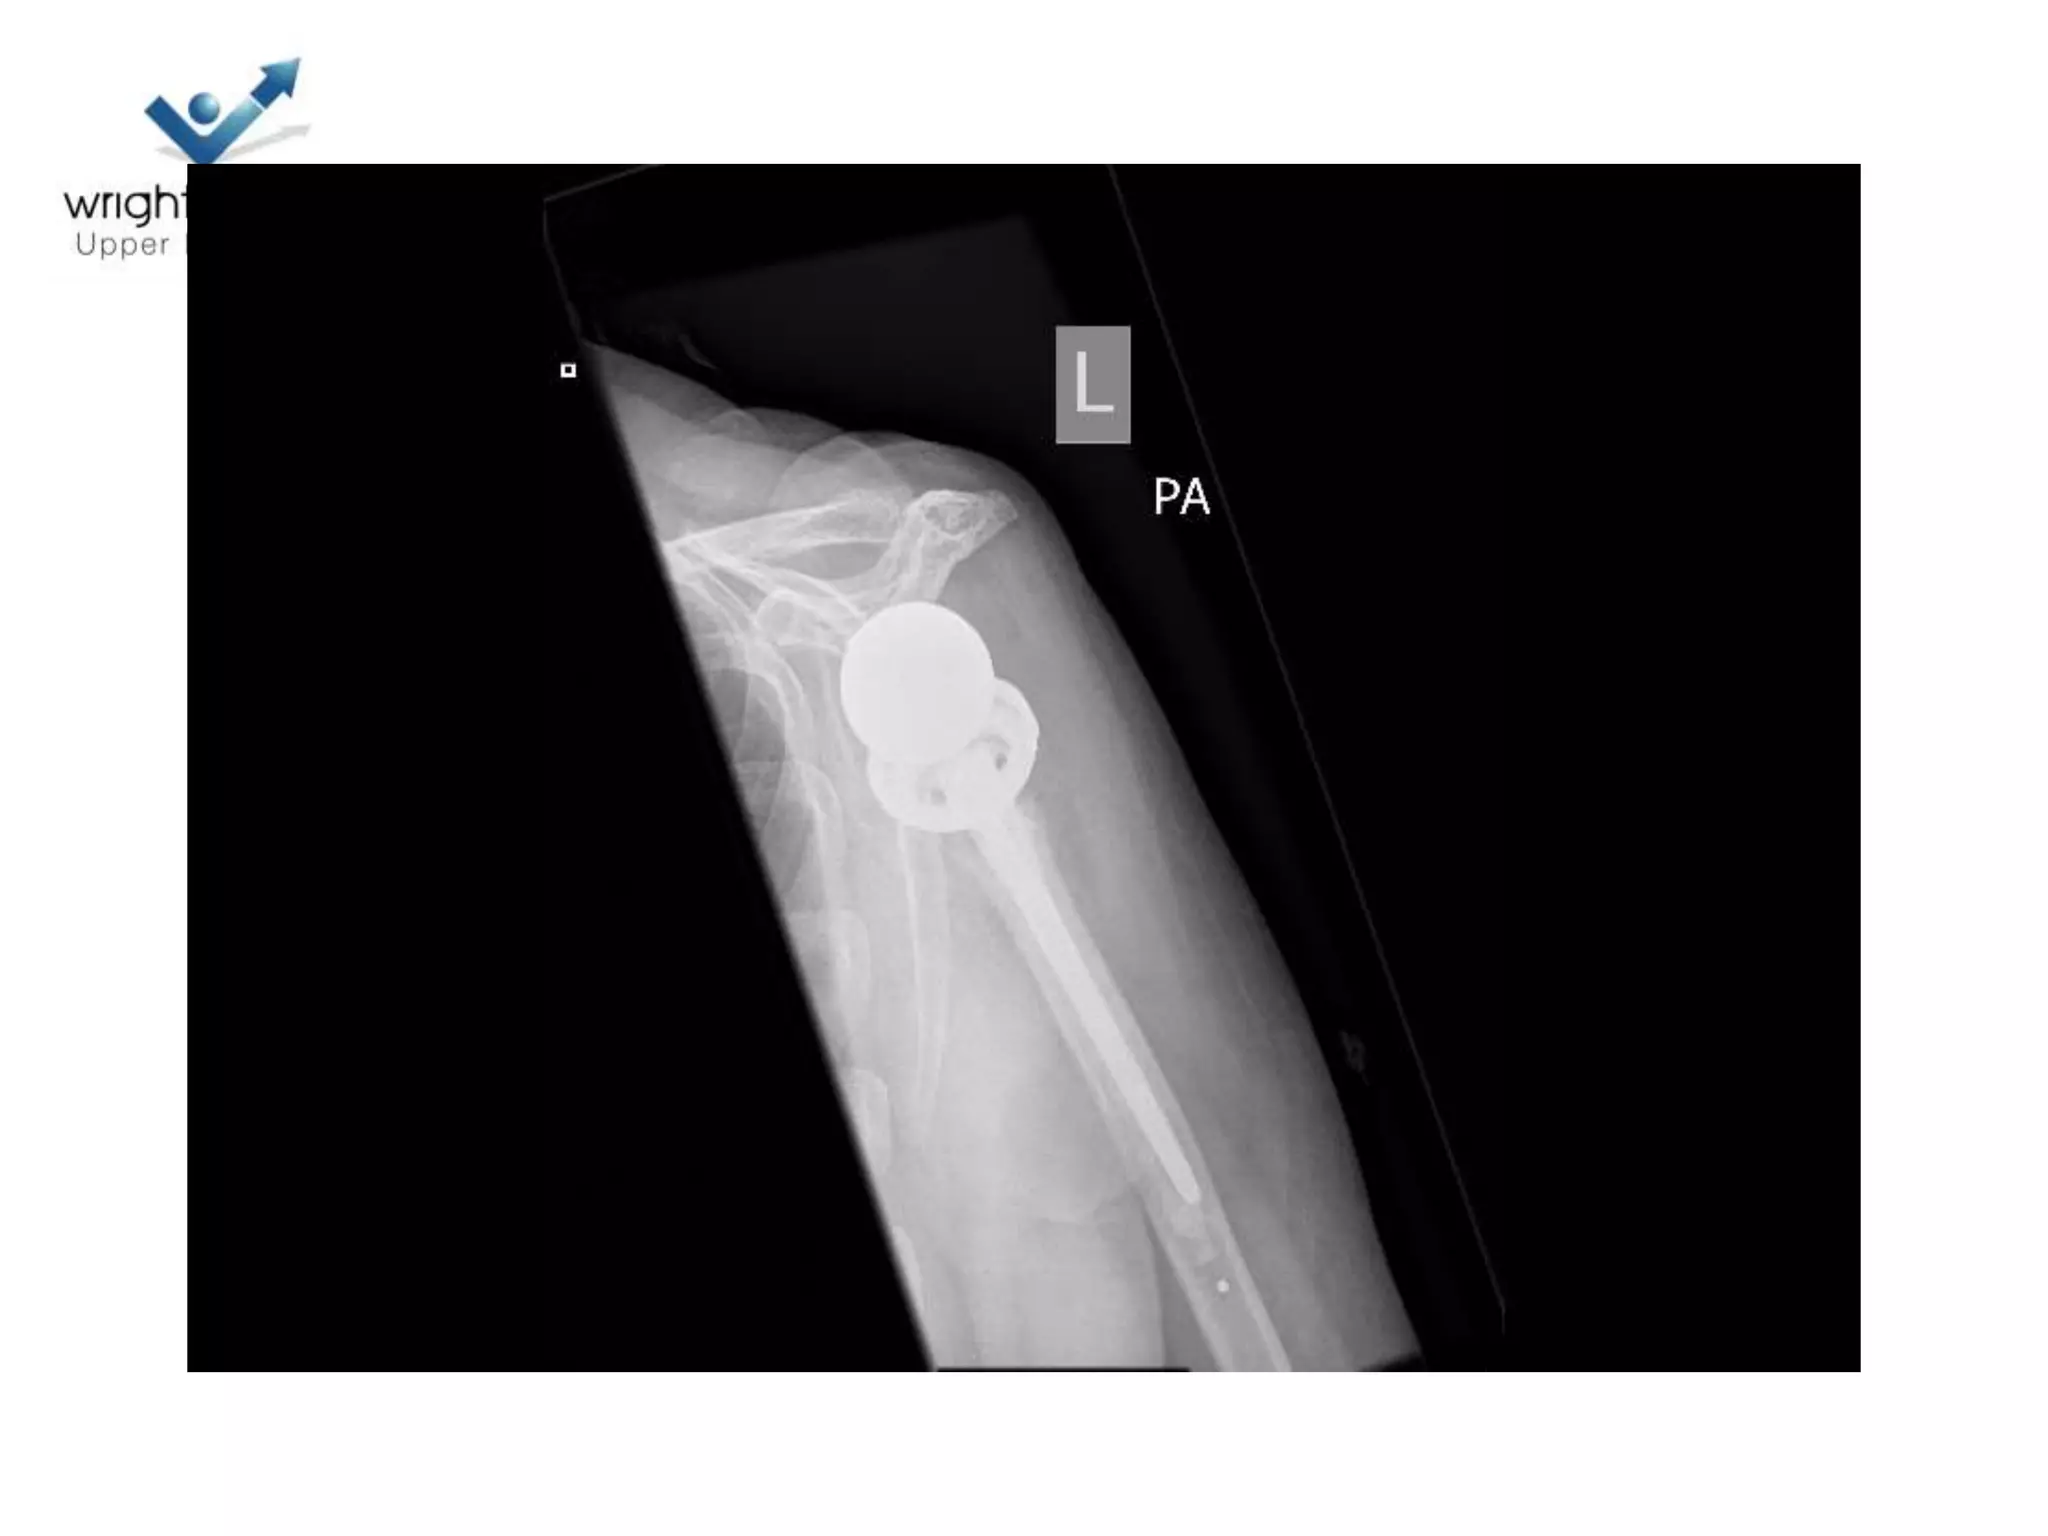

Hemiarthroplasty

• Getting it right

• Depth of prosthesis

• Version of prosthesis

• Size of the head

8 Next